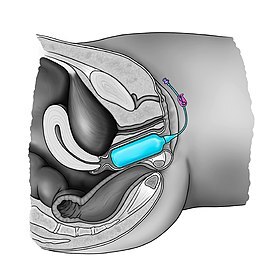

Best Vaginal Tightening surgery treatment in Delhi is an excellent surgery that helps you in getting back your lost charm. Due to frequent intercourse or Pregnancies the vaginal muscle loses its elasticity. This eventually in dissatisfaction between the partners. The Vaginal Tightening surgery treatment in Delhi is an excellent cure for this problem. This vaginal tightening surgery treatment in Delhi helps in providing elasticity to the vaginal muscle. The reconstruction of vagina surgery takes place so that it get back the proper shape

At Vaginal Tightening surgery treatment in Delhi, vaginoplasty is the cosmetic surgical procedure that rejuvenates or corrects a vagina which may have lost its elasticity or shape because of reasons like childbirth or because of aging. A stretched vagina can diminish the satisfaction and comfort levels of both the sexual partner as well as the woman herself. With best vaginal tightening surgery treatment in Delhi, any woman can regain a toned vagina muscle which will cause greater contraction capability and control and it leads heightened sensation for both partners during the sexual experience.

Vaginal tightening surgery is a normal gynecologic surgical procedure. Vaginal tightening surgery treatment in Delhi

aims at tightening the vaginal muscles and surrounding soft tissues. This is achieved by reducing excess vaginal lining and tightening the vaginal canal. After vaginal procedure, the size of vaginal muscles decreases providing greater friction and enhancing the sensation and satisfaction for both partners.

Best Vaginal Tightening surgery treatment in Delhi is an excellent surgery that helps you in getting back your lost charm. Due to frequent intercourse or Pregnancies the vaginal muscle loses its elasticity. This eventually in dissatisfaction between the partners. The Vaginal Tightening surgery treatment in Delhi is an excellent cure for this problem. This vaginal tightening surgery treatment in Delhi helps in providing elasticity to the vaginal muscle. The reconstruction of vagina surgery takes place so that it get back the proper shape

At Vaginal Tightening surgery treatment in Delhi, vaginoplasty is the cosmetic surgical procedure that rejuvenates or corrects a vagina which may have lost its elasticity or shape because of reasons like childbirth or because of aging. A stretched vagina can diminish the satisfaction and comfort levels of both the sexual partner as well as the woman herself. With best vaginal tightening surgery treatment in Delhi, any woman can regain a toned vagina muscle which will cause greater contraction capability and control and it leads heightened sensation for both partners during the sexual experience.

Vaginal tightening surgery is a normal gynecologic surgical procedure. Vaginal tightening surgery treatment in Delhi

aims at tightening the vaginal muscles and surrounding soft tissues. This is achieved by reducing excess vaginal lining and tightening the vaginal canal. After vaginal procedure, the size of vaginal muscles decreases providing greater friction and enhancing the sensation and satisfaction for both partners.